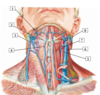

1 - facial artery and vein

2 - retromandibular vein

3 - external jugular vein

4 - anterior jugular vein

5 - common carotid artery

6 - internal jugular vein

7 - superior thyroid artery and vein

8 - external carotid artery

#1

#1 - facial artery and vein

#2

137

#3 - external jugular vein

#4

139

#5 - common carotid artery

#6

141

#7 - superior thyroid artery and vein

#8